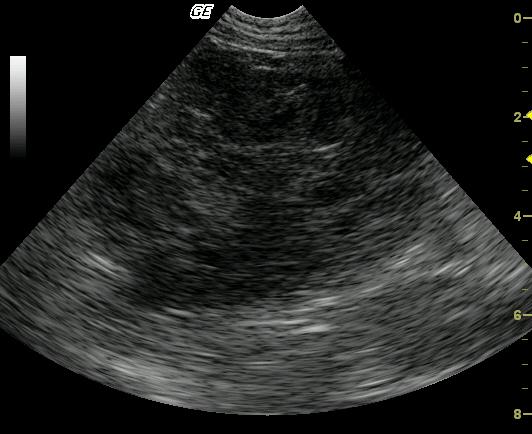

Long-axis view of the left lateral liver lobe reveals a large (5-cm), lobulated, complex, mixed echogenic, nodular mass arising from the left caudal liver. The mass is causing caudal displacement of the stomach, which was not in the view. The remaining left liver demonstrates a mildly echogenic parenchyma with evidence of portal venous congestion.